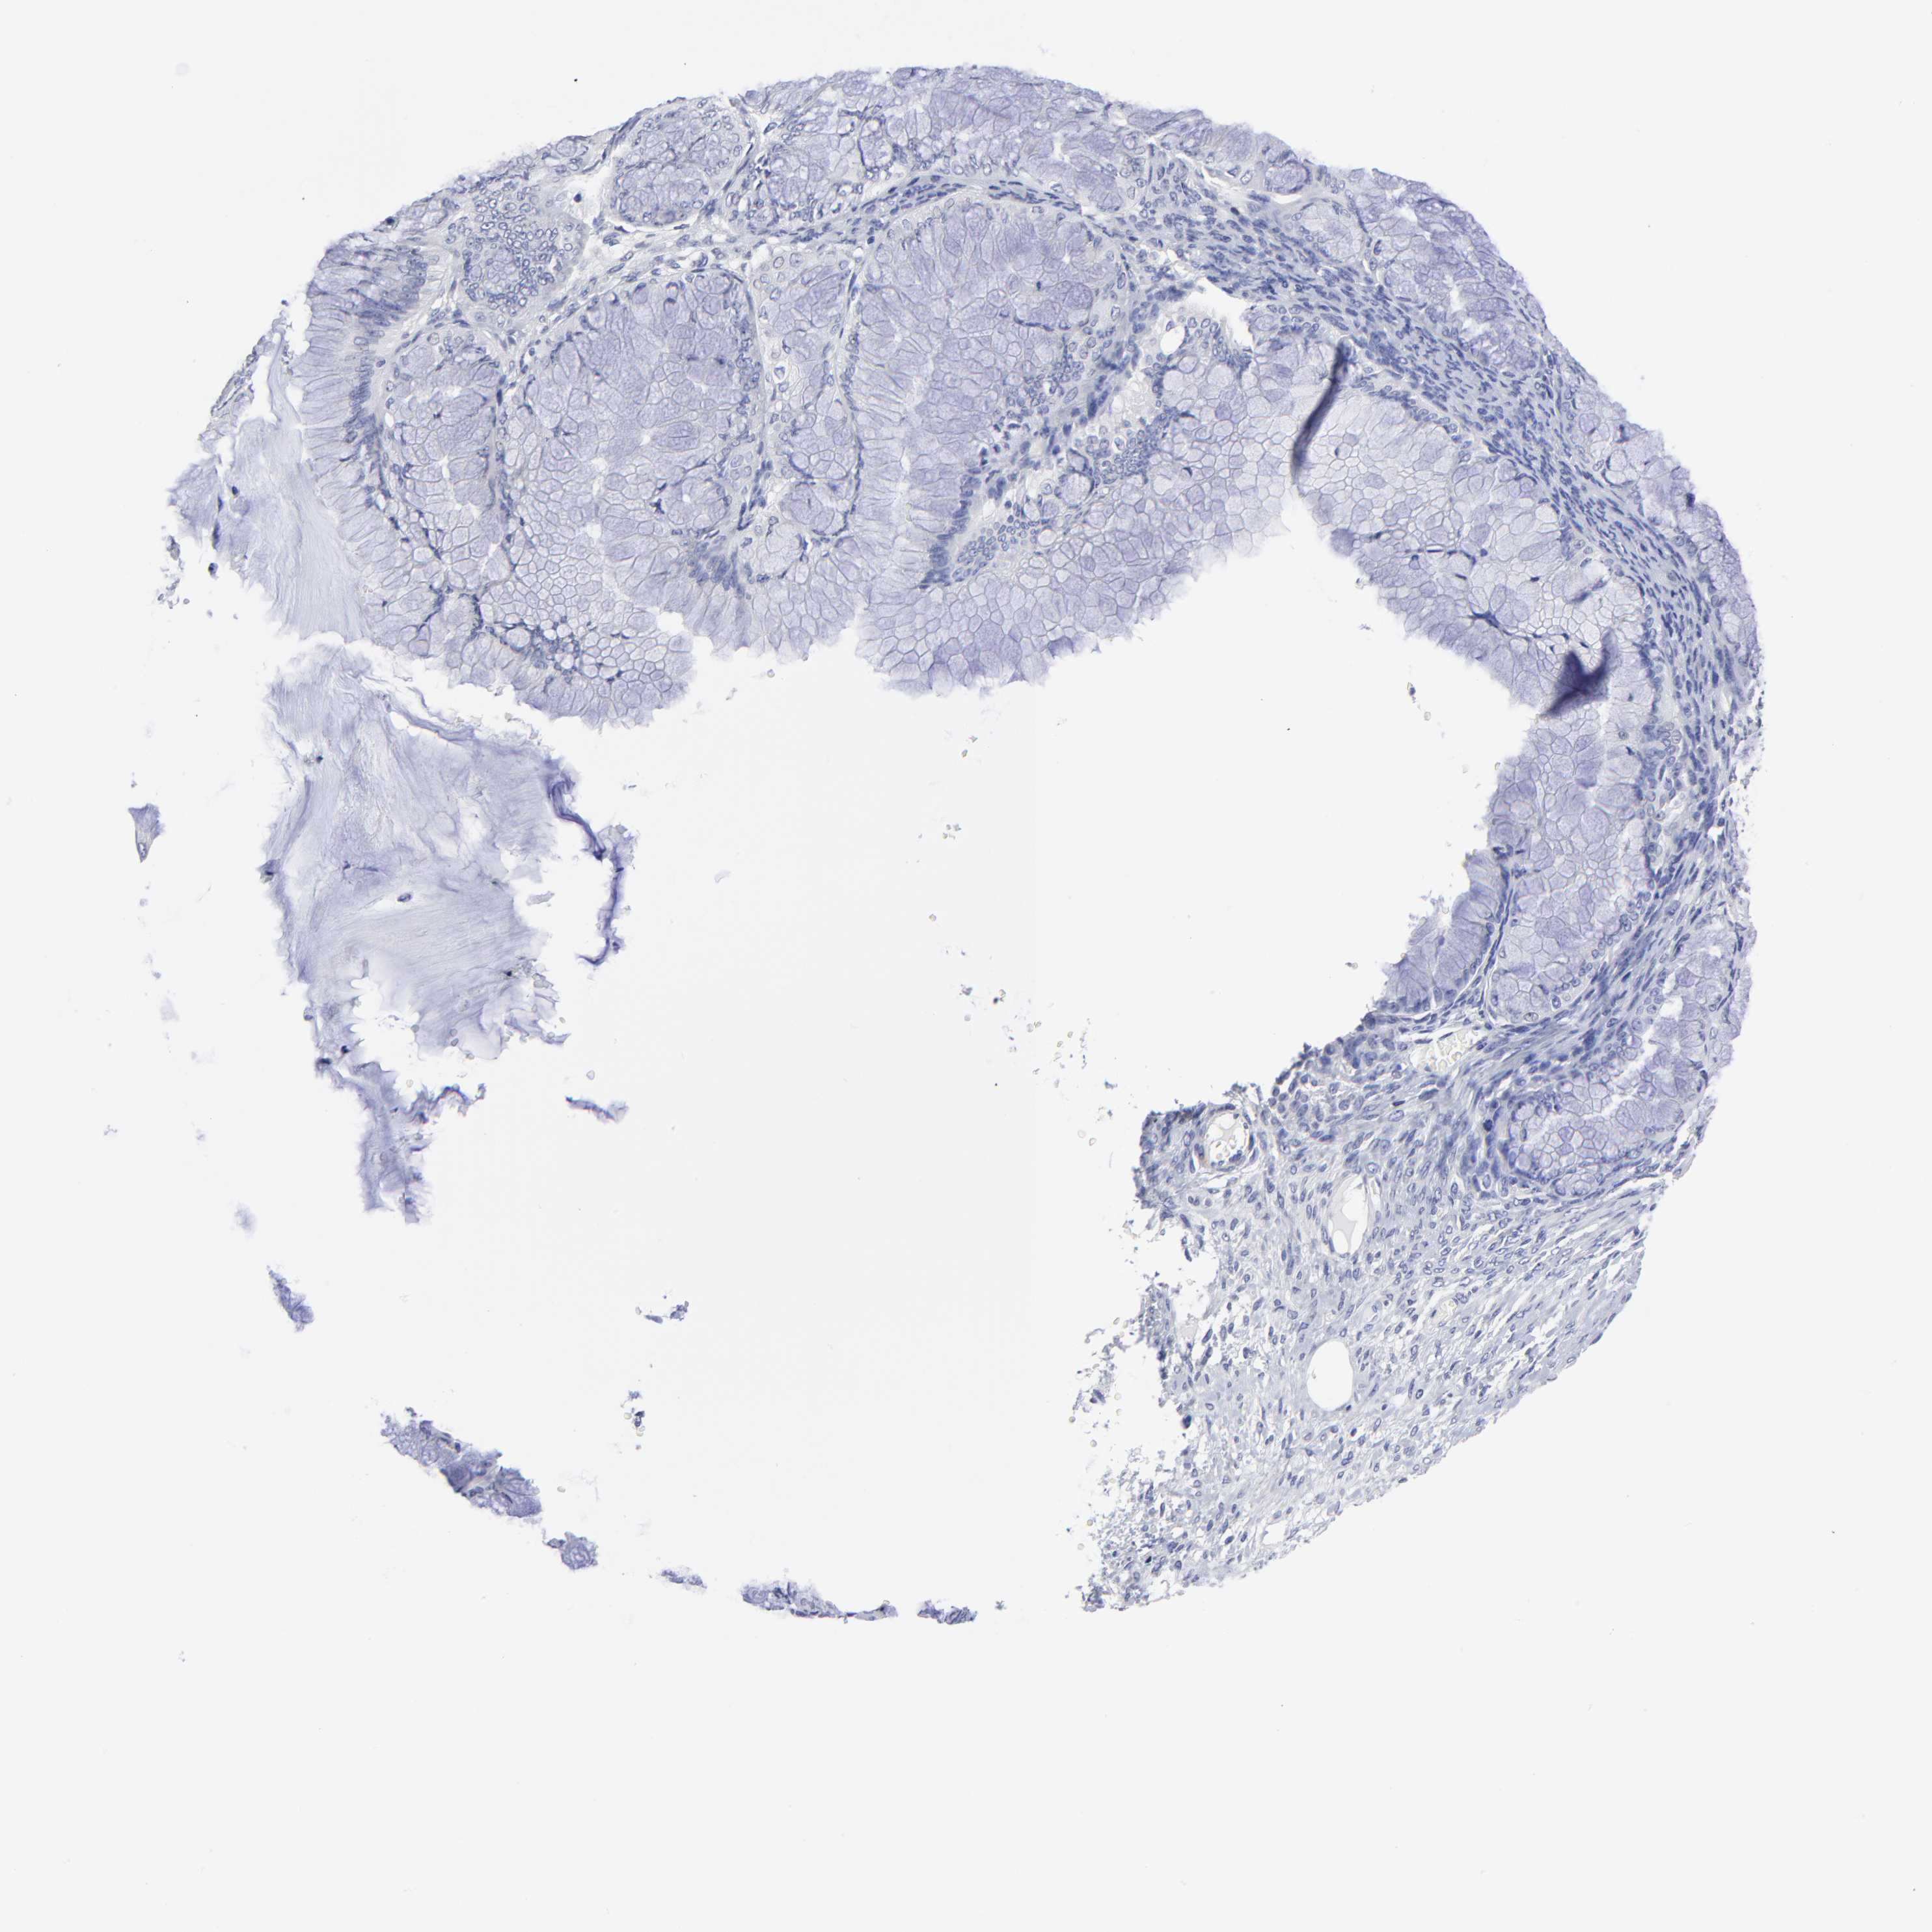

OVARIAN CANCER - Protein expressioni

A mouse-over function shows sample information and annotation data. Click on an image to view it in a full screen mode. Samples can be filtered based on level of antibody staining by selecting one or several of the following categories: high, medium, low and not detected. The assay and annotation is described here.

Note that samples used for immunohistochemistry by the Human Protein Atlas do not correspond to samples in the TCGA dataset.

Antibody stainingi

Antibody staining in the annotated cell types in the current human tissue is reported as not detected, low, medium, or high, based on conventional immunohistochemistry profiling in selected tissues. This score is based on the combination of the staining intensity and fraction of stained cells.

Each image is clickable and will lead to virtual microscopy that enables deeper exploration of all samples and also displays staining intensity scores, fraction scores and subcellular localization as well as patient and tissue information for each sample.

Antibody HPA003336

Carcinoma, endometroid

Cystadenocarcinoma, serous, NOS

Cystadenocarcinoma, mucinous, NOS